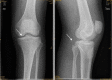

Results: From January 2010 to June 2012, a total of 18 arthroscopically treated cases of PCL tibial avulsion fracture were retrospectively evaluated. Reduction of the avulsion fragment was obtained in all cases. 16 cases were followed up for 7-30 months (average 13.6), and 2 cases were out of follow-up. In the 16 followed patients, flexion and extension were back to normal within 6 weeks, and return to normal walk in 12 weeks. The bone healing was good without any vascular or nerve complications. All the patients regained the preinjury activity level. The mean score (and standard deviation) increased from 38.9 ± 4.9 points to 95.2 ± 3.8 points with the system of Lysholm, from 57.1 ± 10.3 points to 94.3 ± 4.4 points with the system of IKDC. Post-test displacement of KT3000 declined from 3.6 ± 0.39 to 1.1 ± 0.27 mm.

Conclusion: Arthroscopic vertical fixation by high-strength line is a simple, safe, reliable, and micro-invasive treatment to PCL tibial avulsion fracture. It is a kind of real all arthroscopic technique, and good for early postoperative rehabilitation. The total stability of the knee could be gained, and the second operation to remove the internal fixation is avoided.